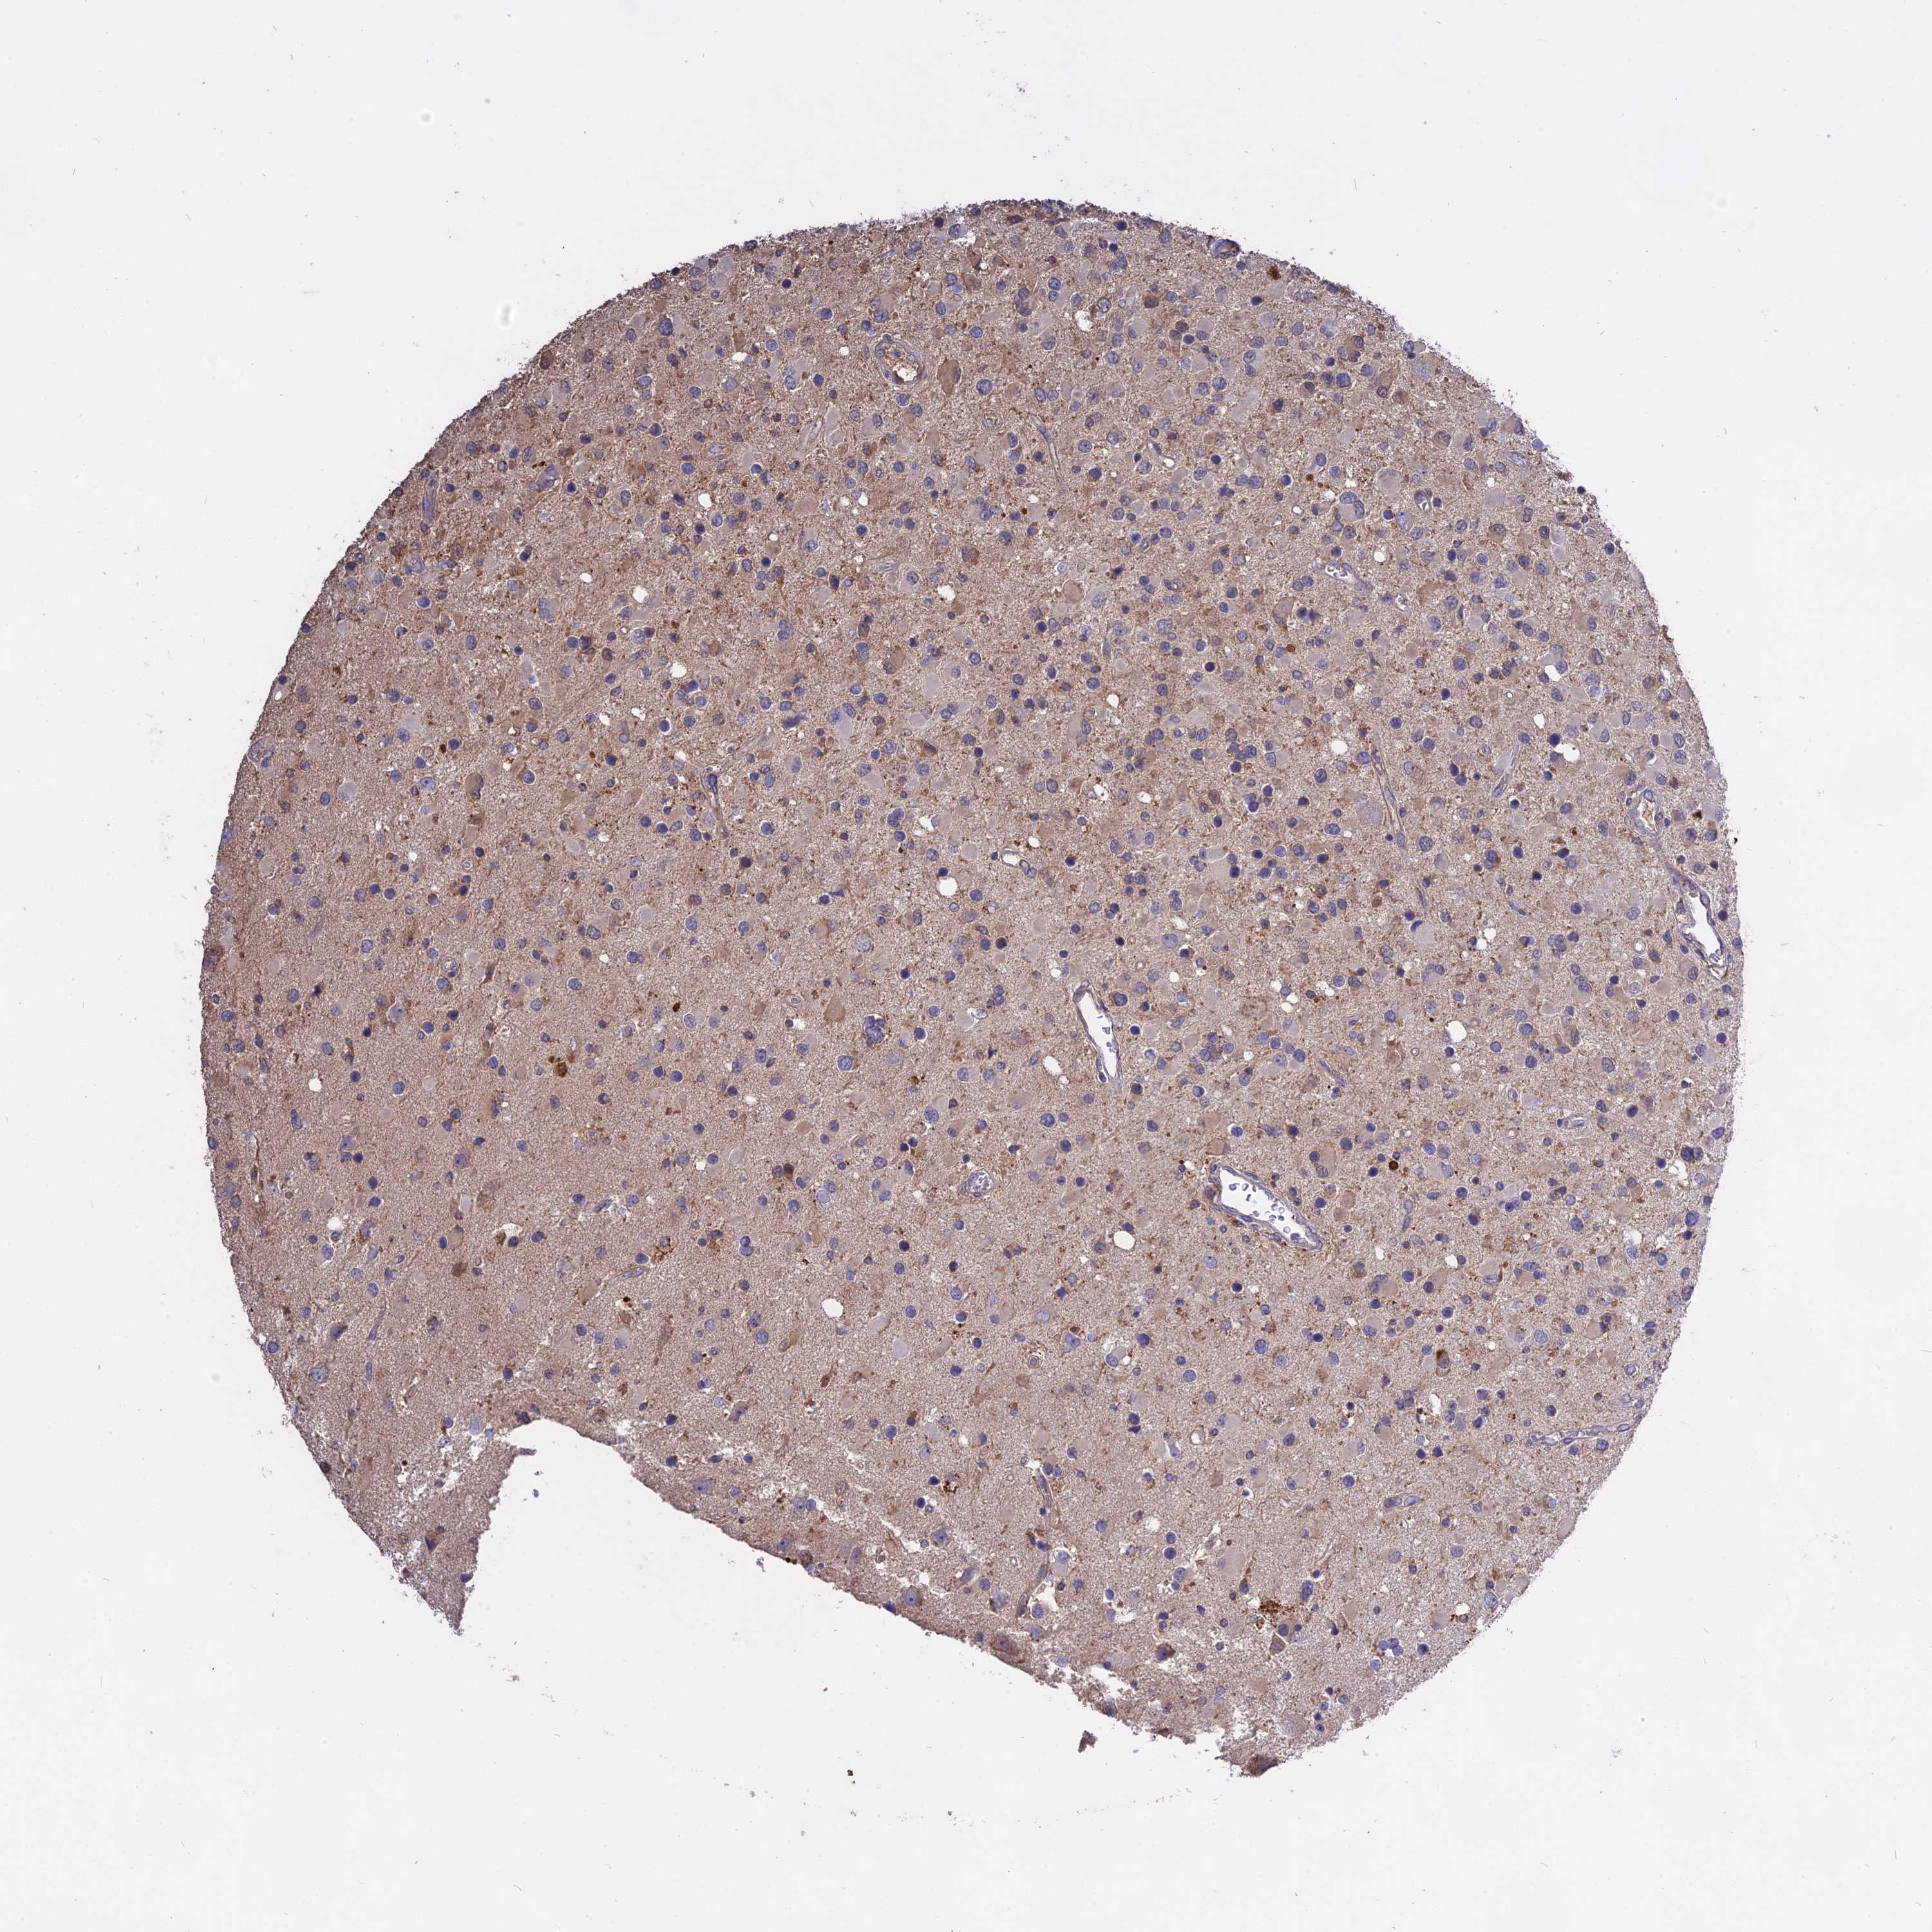

GLIOMA - Protein expressioni

A mouse-over function shows sample information and annotation data. Click on an image to view it in a full screen mode. Samples can be filtered based on level of antibody staining by selecting one or several of the following categories: high, medium, low and not detected. The assay and annotation is described here.

Note that samples used for immunohistochemistry by the Human Protein Atlas do not correspond to samples in the TCGA dataset.

Antibody stainingi

Antibody staining in the annotated cell types in the current human tissue is reported as not detected, low, medium, or high, based on conventional immunohistochemistry profiling in selected tissues. This score is based on the combination of the staining intensity and fraction of stained cells.

Each image is clickable and will lead to virtual microscopy that enables deeper exploration of all samples and also displays staining intensity scores, fraction scores and subcellular localization as well as patient and tissue information for each sample.

Antibody HPA041252

Antibody HPA041466

Glioma, malignant, High grade

Glioma, malignant, Low grade